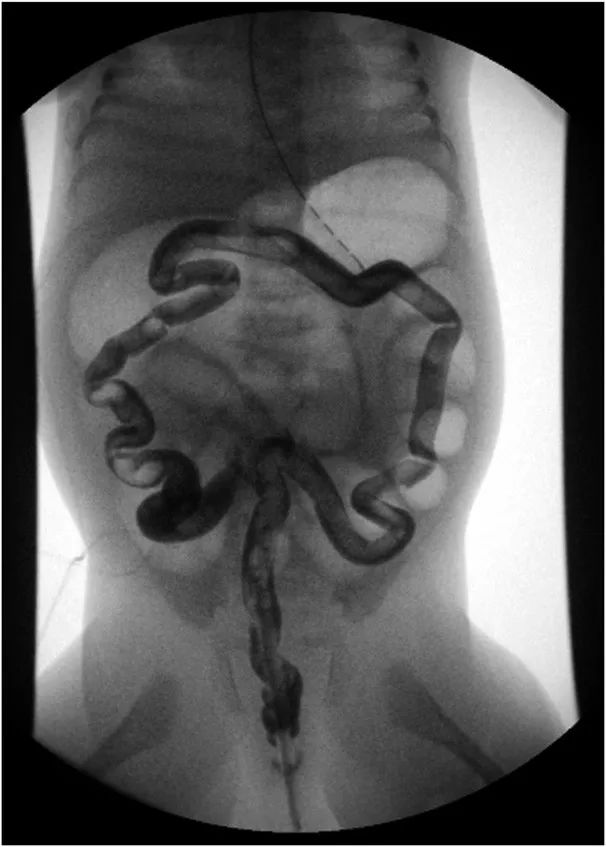

考虑到婴儿患有先天性巨结肠疾病,胎粪延迟排出超过24小时,以及远端肠梗阻的腹部影像学改变,进行了灌肠对比剂造影检查(图2)。

先天性细小结肠症

(congenital microcolon)

又称胎儿结肠,是新生儿肠梗阻所引起的继发征象。因结肠细小幼稚,管径<1.0 cm而得名,由一组先天性消化道畸形引起,常见于肠闭锁、胎粪性畅梗阻和全结肠型无神经节细胞症,属于一种少见的新生儿先天性肠道畸形。